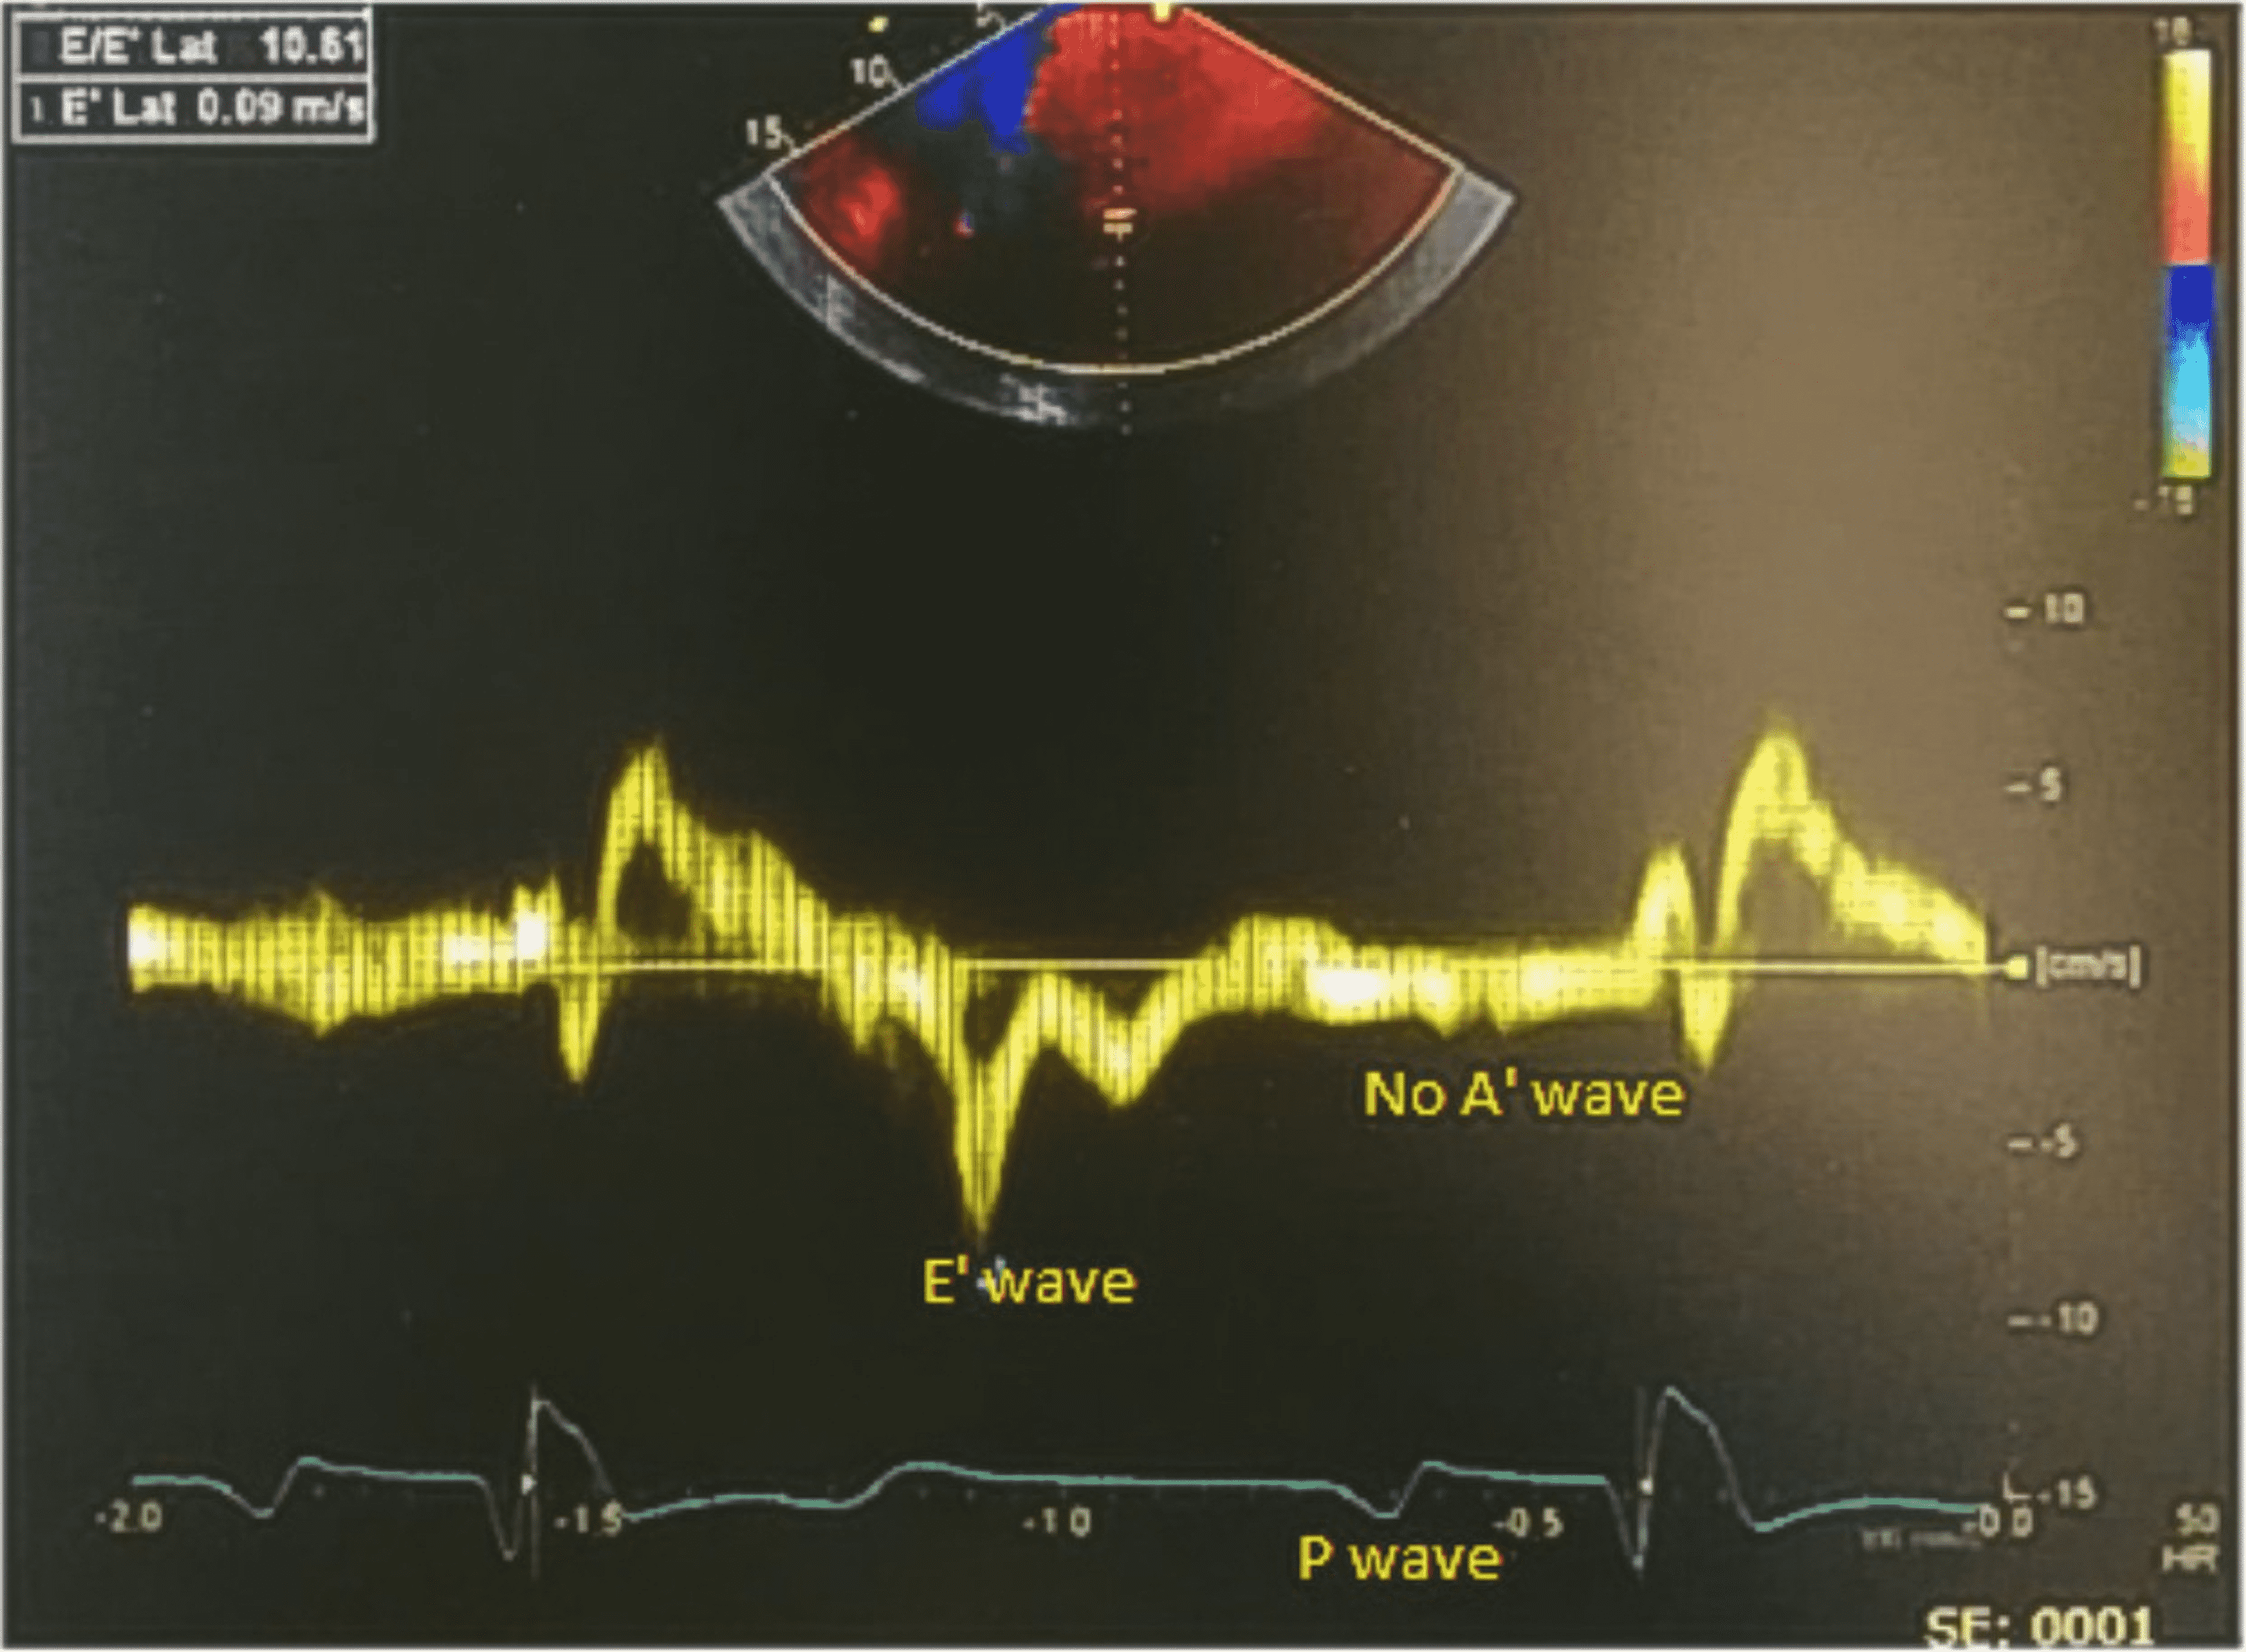

Cureus Persistent Atrium Standstill Post Atrial Fibrillation Ablation

Cureus Persistent Atrium Standstill Post Atrial Fibrillation Ablation Standstill Disease It is well documented that some patients with a. Atrial standstill is a rare cardiac rhythm disease with a few familial and sporadic cases described to date that is characterized by a transient or permanent. The term sinoatrial disease is used interchangeably with sick sinus syndrome and describes a series of abnormalities that can result in profound sinus bradycardia, sinus. Standstill Disease.

Cureus Persistent Atrium Standstill Post Atrial Fibrillation Ablation Standstill Disease Atrial standstill is a rare condition in which the atrium loses its mechanical contraction with or without losing the electrical conduction. It is well documented that some patients with a. The term sinoatrial disease is used interchangeably with sick sinus syndrome and describes a series of abnormalities that can result in profound sinus bradycardia, sinus pauses, sinus arrest, sinoatrial nodal. Standstill Disease.